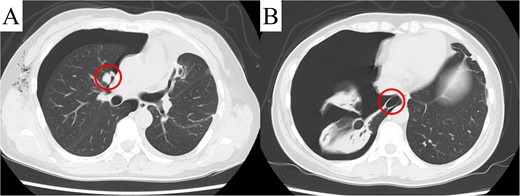

Computed tomography revealed a solitary pulmonary nodule (circle) in the left upper lobe 6 months after uterine surgery.

Despite a mild right pneumothorax on admission, the patient underwent a safe operation with chest drainage for the right pneumothorax. Intra-operative findings revealed a bulla at the apex of the left lung and unexpected pleural dissemination (Fig. 3A and B). Therefore, we performed a pulmonary metastasectomy and a pleural biopsy with bullectomy for diagnostic purposes. The patient was discharged without complication or exacerbation of the pneumothorax. However, recurrence of the right pneumothorax was observed four days after discharge, and surgery was scheduled. CT revealed a pleural dissemination nodule in the right hilar area and a bulla in the right lower lobe, in addition to the right pneumothorax (Fig. 4A and B). Intra-operatively, we identified a pleural dissemination nodule in the right hilar area with moderate air leakage, and resection was performed (Fig. 5A). The bulla in the right lower lobe was also resected (Fig. 5B).

Computed tomography revealed a pleural dissemination nodule in the right hilar area (A) and a bulla in the right lower lobe (B). The findings are indicated by circles.